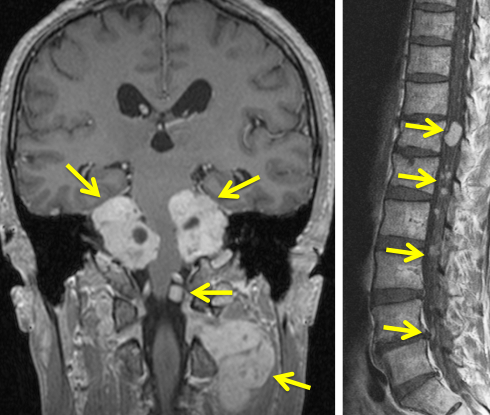

脳と腰部のガドリニウム増強MRIです。腫瘍は白く見えるようにしてあります。黄色の矢印で示した以外にも無数の神経鞘腫があります。

赤の矢印が,両側の聴神経腫瘍です。黄色の矢印は, 多発性の髄膜腫です。蝶形骨縁髄膜腫,穹隆部髄膜腫,大脳鎌髄膜腫,大脳鎌テント接合部髄膜腫などいっぱいあります。これらは基本的に経過観察しますが,とても目立って大きくなるものがあれば摘出します。摘出には注意が必要で,近い将来また手術になるかもしれないので,次回の手術もできるように工夫して開頭手術しなければなりません。でないと,次の手術での合併症が増えます。また一回の開頭で近傍の硬膜や腫瘍を可能な限り摘出してしまうことも大切です。でないと,限りなく手術を繰り返すことになります。